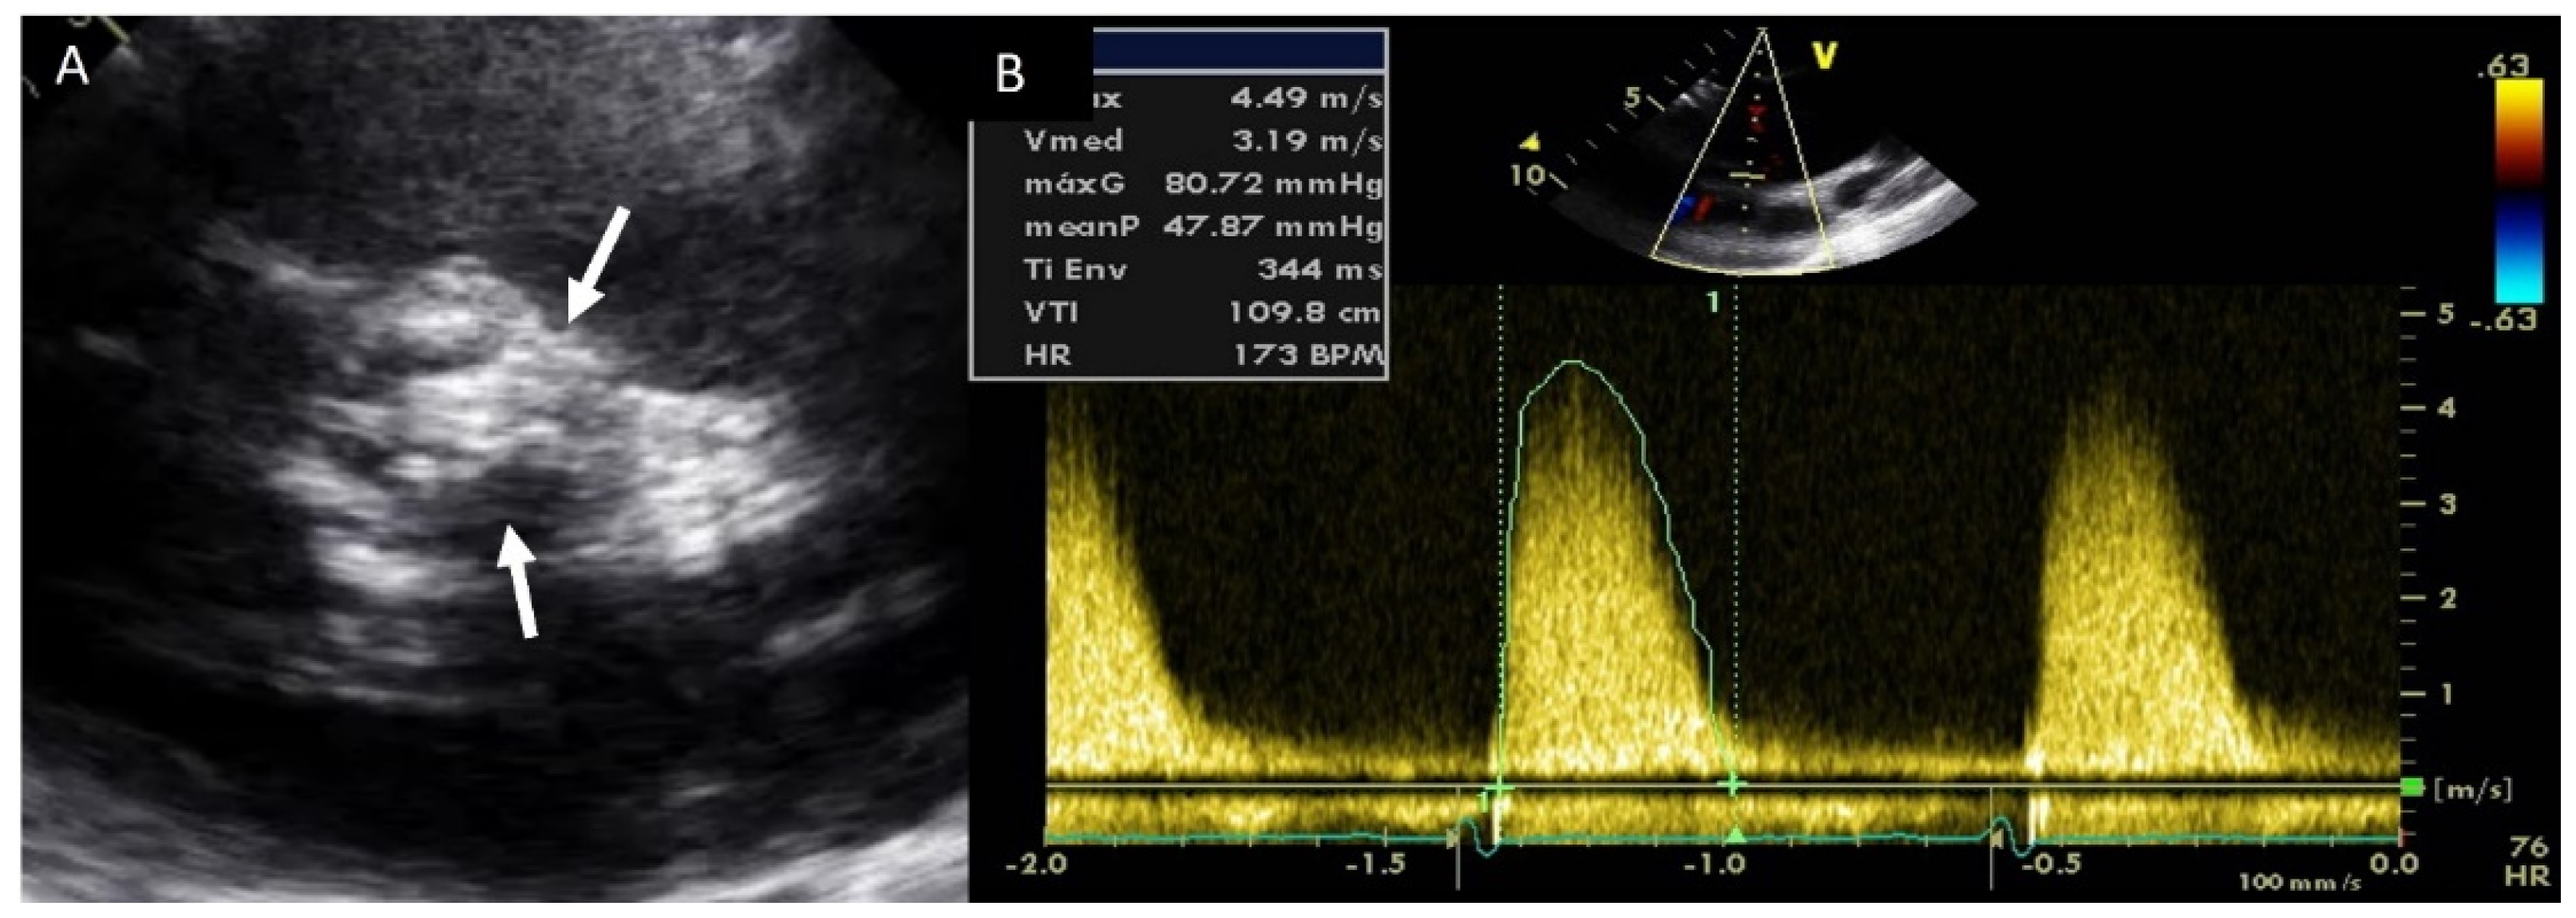

Adults diagnosed with BAV have a clear increased risk of developing AS, usually secondary to leaflet calcification. Previous studies have showed that over 15 years of follow up, 12.3% of the cohort required aortic valve replacement for severe AS [32]. In our daily practice, TTE is the most used technique for evaluating the presence of this complication, and for guiding appropriate management. AS quantification is based on the same parameters of tricuspid valves (Figure 4). We must remember that the aortic valve area may be significantly underestimated by TTE owing to underestimation of aortic annulus measurement. However, the use of CTA may correct these underestimations [1].

Figure 4.

Severe aortic stenosis in BAV with severe calcification (arrows) (A); the mean gradient by continuous-wave Doppler is 48 mmHg (B).